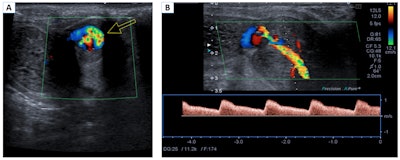

Priapism occurs when a pathological penile erection persists for four hours or more and is not related to sexual stimulation. It is classified as low-flow priapism (ischemic or veno-occlusive) and high-flow priapism (not ischemic or arterial). Imaging tests are not usually necessary, and cavernous blood gas levels can help to confirm the diagnosis, the Madrid team stated.

Nonischemic or high-flow priapism. Color Doppler in the transverse plane (A) and spectral Doppler in the longitudinal plane (B). Turbulent flow of the left cavernous artery is observed (arrow). The lesion shows a low resistance pattern, with increased systolic and diastolic velocities. These findings are related to a penile pseudoaneurysm.